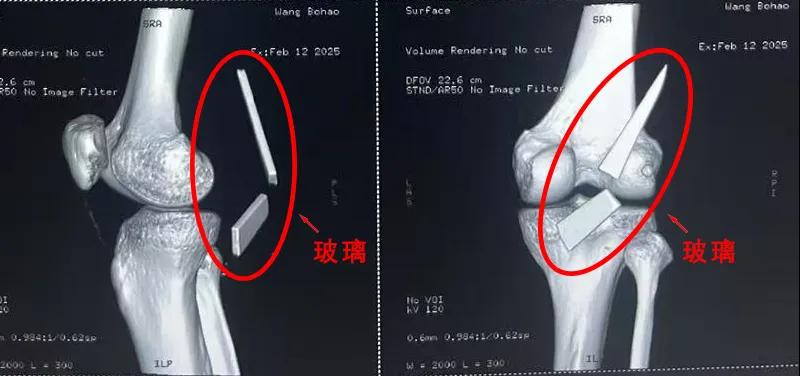

13厘米碎玻璃扎入腿中,漯河醫(yī)專二附院顯微外科緊急“拆彈”......

患者家屬這才開始意識到問題的嚴(yán)重性,便帶著孩子到鄉(xiāng)鎮(zhèn)衛(wèi)生院檢查——結(jié)果顯示右膝關(guān)節(jié)后方竟然殘留著兩塊兒鋒利的碎玻璃,測量后預(yù)估玻璃總長將近13厘米!

由于玻璃位置毗鄰坐骨神經(jīng)和股動(dòng)脈,一旦刺破股動(dòng)脈,將嚴(yán)重威脅生命。家屬著急萬分,想著能否盡快手術(shù)取出碎片,于是慕名來到漯河醫(yī)專二附院(漯河市骨科醫(yī)院、漯河市立醫(yī)院)手顯微外科(修復(fù)重建骨感染科)。

術(shù)中,馬廣輝醫(yī)生憑借扎實(shí)的理論知識和嫻熟的顯微外科技術(shù),順利找到深深刺進(jìn)肌肉的兩塊玻璃,肉眼可見玻璃尖端距股動(dòng)脈僅有不到半公分的距離!如果患者再耽誤半天或者再多活動(dòng)幾次膝關(guān)節(jié),小指粗的股動(dòng)脈很有可能被玻璃扎破,后果難以想象。

最終,馬廣輝醫(yī)生在血管、神經(jīng)表面順利取出兩塊玻璃碎片,拆除了埋在患者膝關(guān)節(jié)的“炸彈”。在告知患者家屬術(shù)中情況后,家屬懸著的心終于放了下來。